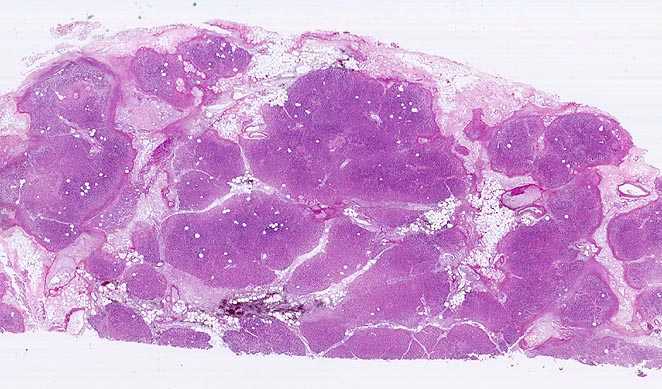

akute Pankreatitis

Pankreasparenchym und Fettgewebe werden von unregelmässigen Nekrosestrassen durchzogen. Bevorzugt ist das interlobuläre Fettgewebe von den autodigestiven Nekrosen betroffen. Die Nekroseareale werden gegen aussen begrenzt durch einen feinen hämorrhagischen Randsaum. Zentrale Parenchymanteile (violett) sind noch vital.

Bekannter Ethylabusus. Nach einem Alkoholexzess kam der Patient wegen heftigster epigastrischer, in den Rücken ausstrahlender Abdominalschmerzen und orthostatischer Hypotonie auf die Notfallstation. 60 Stunden nach Spitaleintritt entwickelt der Patient ein Multiorganversagen und verstirbt.